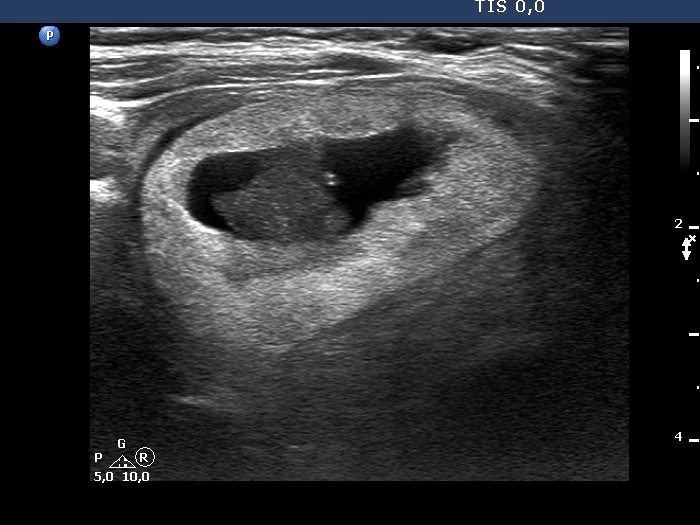

Second examination 3 years later (second row of images):

Clinical presentation. The patient came to routine follow-up visit. She has lost her husband for three months and thereafter diffuse complaints including weight loss, anxiety and sleep disturbance had evolved.

Palpation: unchanged.

Result of blood test: TSH 5.61 mIU/L.

Ultrasonography. The right cystic nodule has in part refilled. Otherwise, the presentation remained unchanged.Suggestion: TSH determination in 6 months, ultrasound in 3 to 5 years.

This case illustrates how a spongiform type cyst might evolve from a central-type cystic nodule. See video and longitudinal scans of the right lobe.

The nodule has tiny hypoechoic areas, therefore the lesion can be regarded as an EU-TIRADS 4 lesion. Nevertheless, the hypoechoic areas do not raise the possibility that they would represent another pathological entity, therefore, is seems to be more accurate to classify the nodule as an EU-TIRADS 3 lesion.